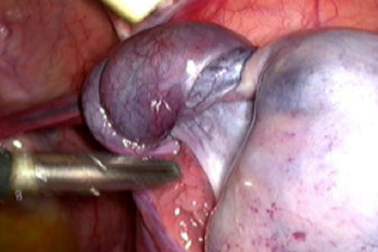

Đau bụng âm ỉ, coi chừng mắc bệnh lý nguy hiểmNhập viện vì đau bụng âm ỉ, nữ bệnh nhân được bác sĩ phát hiện bị phình động mạch lách dọa vỡ. Bằng kỹ thuật can thiệp nội mạch, vị trí túi phình được bác sĩ gây tắc giúp người bệnh qua nguy kịch.